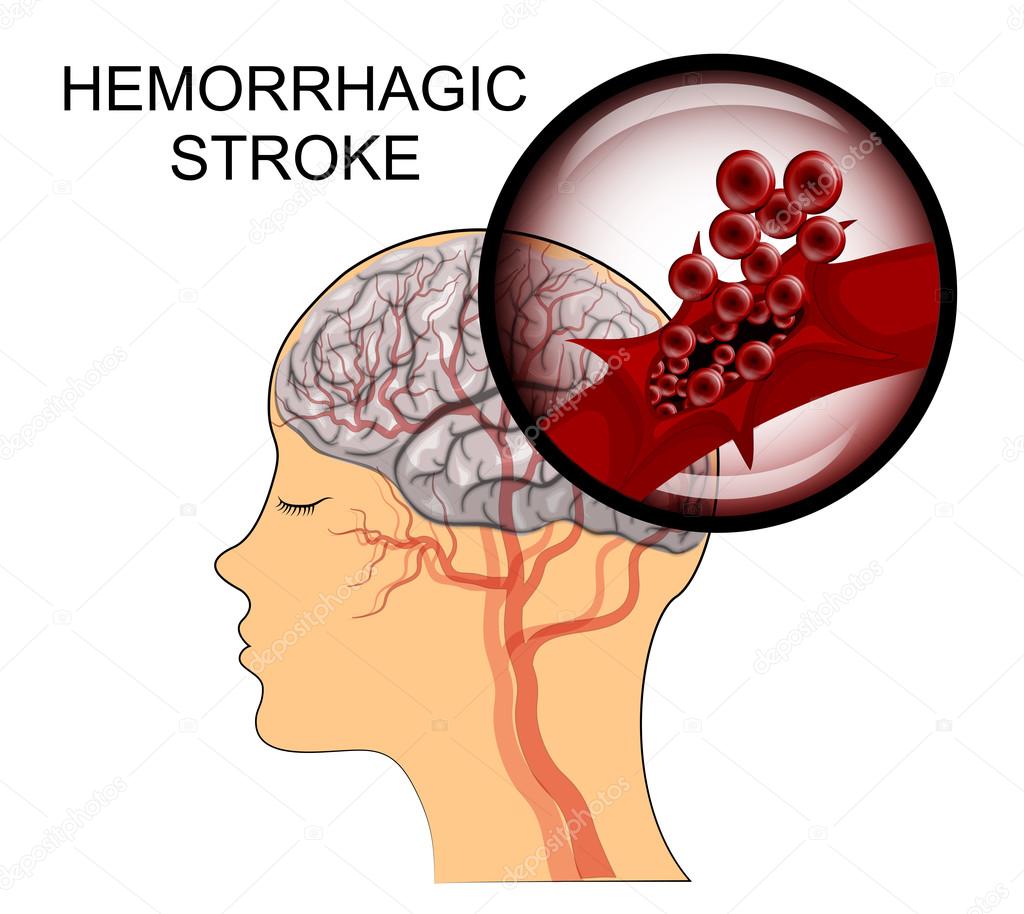

Diagrama que muestra hemorragia cerebral humana. 434335 Vector en Vecteezy

Source: es.vecteezy.com